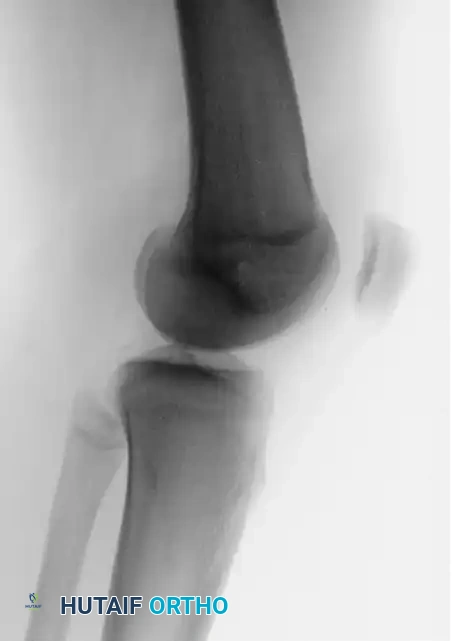

Preoperative imaging must include weight-bearing anteroposterior (AP), lateral, and Merchant (axial) views of the knee, alongside a CT scan to accurately measure the TT-TG distance and assess rotational profiles.

FIGURE 47-18A: Preoperative lateral radiograph demonstrating patellofemoral alignment prior to the Fulkerson procedure.